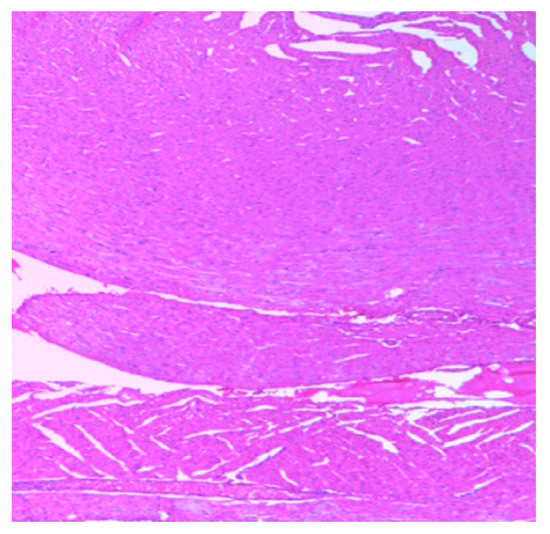

The histology of the hearts of the rat models examined is shown in Figure 13, Figure 14, Figure 15, Figure 16 and Figure 17. Gestation had no histological changes in the cardiac tissues (Figure 14 and Figure 15), while clay beverage consumption during both early and late gestation caused inflammation (Figure 16) and necrosis (Figure 17) of cardiac tissues. We deduce that the functional integrity of the cardiovascular system is at risk during gestation if clay beverage is part of nonfood substances frequently consumed.

Figure 13.

Histopathologic slide of the heart muscle of control rats showing no obvious atypical or reactive change in histology.

Figure 14.

Histopathologic slide of the heart muscle of rats during early gestation stage showing no obvious atypical or reactive change in histology.

Figure 15.

Histopathologic slide of the heart muscle of rats during late gestation stage showing no obvious atypical or reactive change in histology.